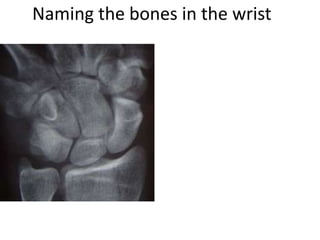

This document provides an overview of hand anatomy including:

- Naming the bones, joints, tendons, nerves and skin landmarks of the hand and wrist.